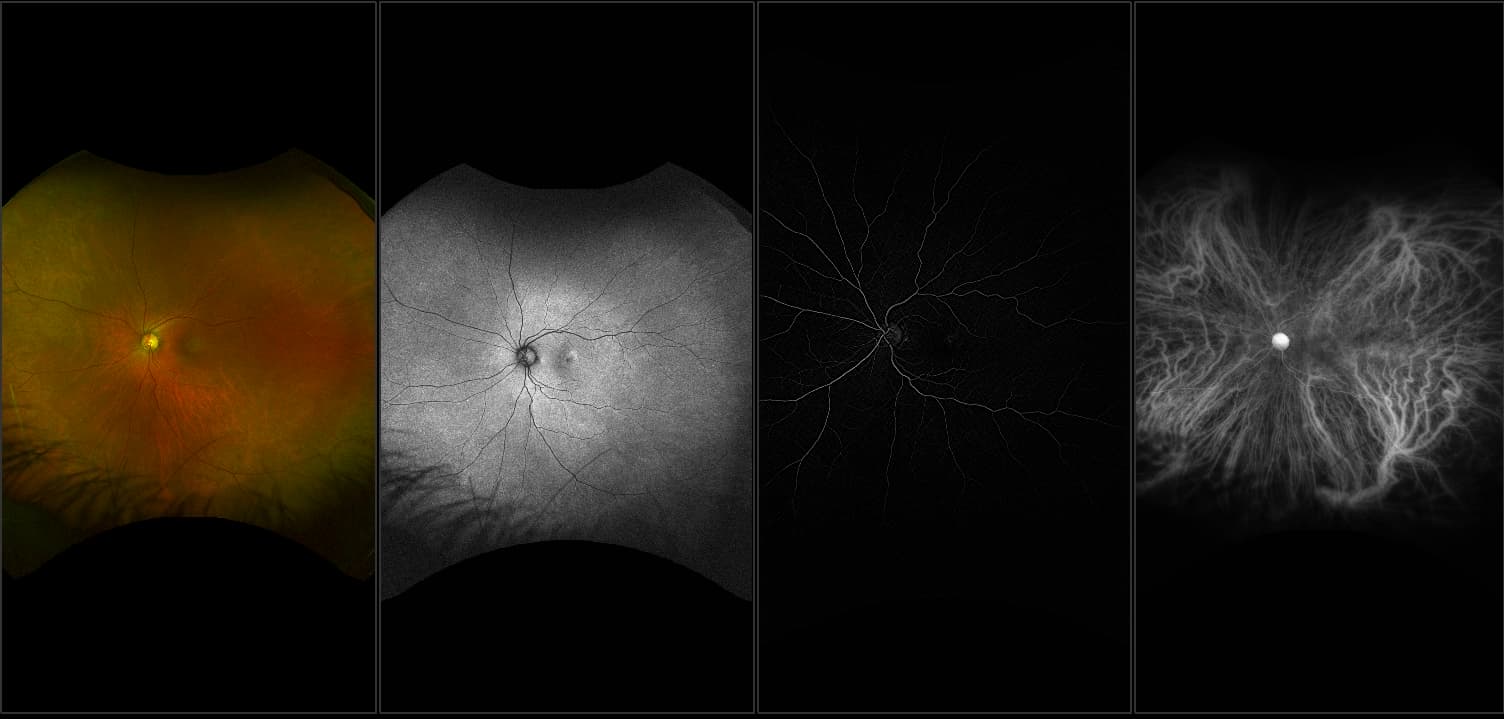

Acute multifocal placoid pigment epitheliopathy (AMPPE)

AMPPE affects otherwise young healthy adults and presents as a disorder affecting the retina, Retinal Pigment Epithelium and choroid. APMPPE is an acquired, self-limiting, inflammatory disorder.